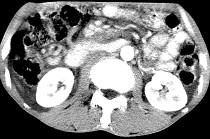

问题 女,50岁,中上腹疼痛,消瘦乏力,影像检查如下图,最佳的诊断是 ( )

选项 A.慢性胰腺炎 B.急性胰腺炎 C.胰腺癌并腹膜后淋巴结转移 D.胰岛素瘤 E.腹膜后淋巴瘤

答案 C